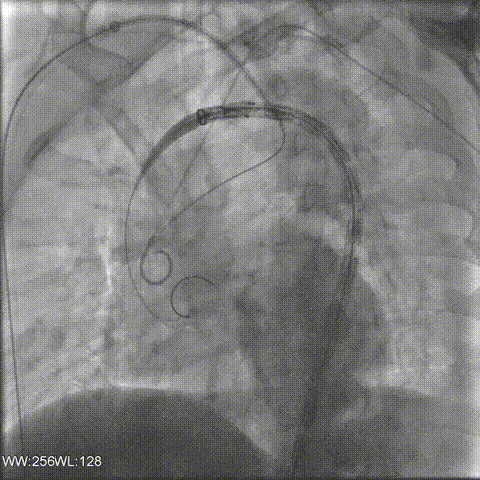

置入覆膜大支架;

右锁骨下动脉置入Viabahn和Smart Control支架(烟囱);

左侧置入Viabahn支架(烟囱);

术后造影复查,右侧迷走锁骨下动脉的烟囱支架角度平顺,血流通畅。